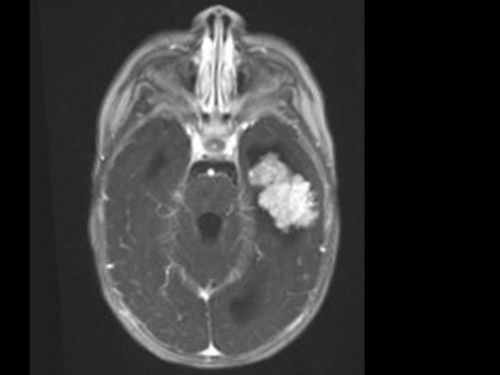

10 Monate altes Mädchen. Der Kinderarzt stellt fest, dass das kleine Mädchen einen recht großen Kopfumfang hat, nicht mit den Augen fixiert und anscheinend auch nicht richtig sehen kann. Damit bestätigt er die größten Befürchtungen der Eltern, denen in den letzten Wochen aufgefallen war, dass ihre Tochter nach keinem Spielzeug mehr greift und sie nur dann anlächelt, wenn sie zu ihr sprechen.

Bildgebung - MRT